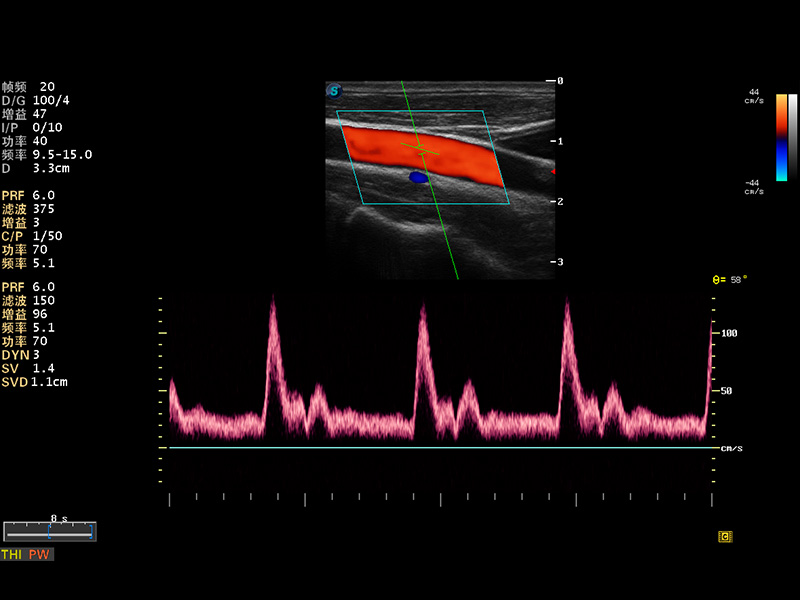

S8 EXP便携式彩色多普勒超声诊断仪是米兰官方网站研发的高端全身应用型便携彩超。高通道的VIS平台融合可视化(Visual)、智能化(Intelligent)和人性化(Smart)的特点,配以米兰官方网站自主研发生产的探头大家族,使您能够快速、准确的获得病人信息,提高工作效率的同时减轻疲劳。

成像技术

多波束形成器